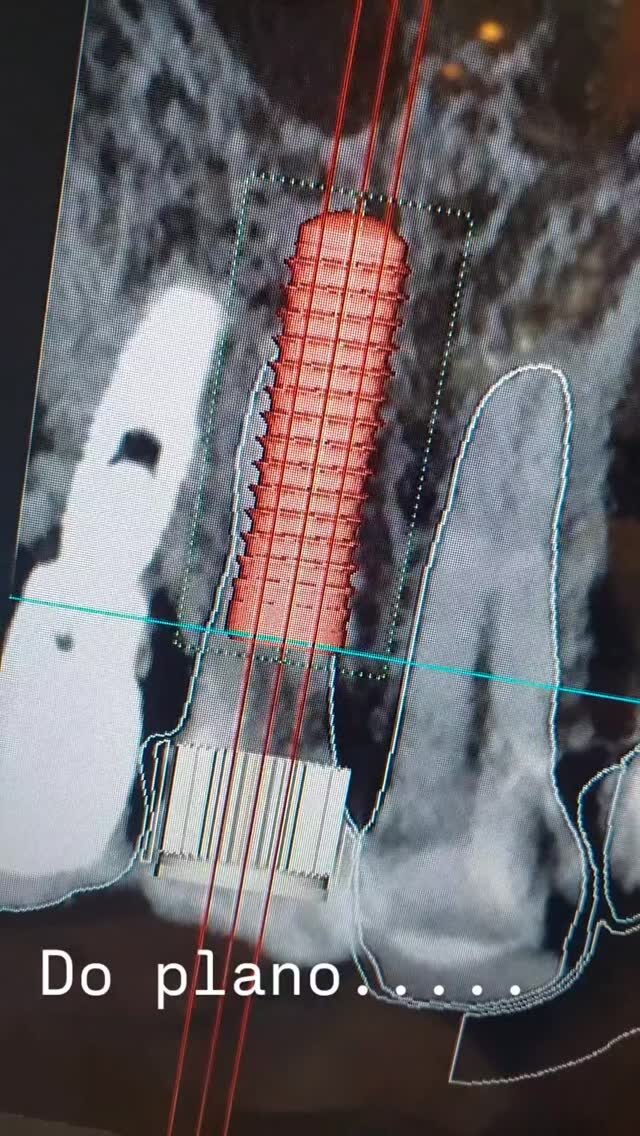

Os implantes dentários substituem dentes perdidos por meio de pinos de titânio inseridos no osso maxilar ou mandibular, que suportam próteses fixas. Proporcionam estética e funcionalidade semelhantes aos dentes naturais, sendo uma solução duradoura e segura.

Dr. Guilherme Rosetti é Cirurgião Bucomaxilofacial e Especialista em Harmonização Orofacial, com sólida formação nacional e internacional. É graduado em Odontologia pela Universidade Federal do Paraná (UFPR) e especialista em Cirurgia e Traumatologia Buco-Maxilo-Facial pela PUC-RS. Possui pós-graduações em Cirurgia Oral Menor (ABO-PR), Artroscopia da ATM (IECS) e Cirurgia Ortognática Minimamente Invasiva (ITC), além de fellowship em Cirurgia da ATM pela JRG Odontologia. É também especialista em Harmonização Orofacial com registro oficial pelo CFO, com formação em Toxina Botulínica e Preenchimento Orofacial pelo Instituto Ziroldo. Conta com diversas habilitações técnicas, incluindo Ozonioterapia, Laserterapia, Sedação Consciente e Venopunção com I-PRF. Completou treinamentos de alto nível como o Virtual Planning in Orthognathic Surgery pela KLS Martin (Alemanha), o L1 MI Orthognathics – ITC Brasil e o curso da SORG Academy em Viena (Áustria), voltado à Cirurgia da ATM. É membro do Colégio Brasileiro de CTBMF e da Latin American Society of TMJ Surgeons (LASTMJS). Com mais de 20 anos de experiência, atua nos principais hospitais de Curitiba, sendo referência nacional em cirurgia ortognática, cirurgia da ATM, implantes, reconstruções ósseas e harmonização facial avançada, com foco em precisão técnica, estética e recuperação funcional de excelência.